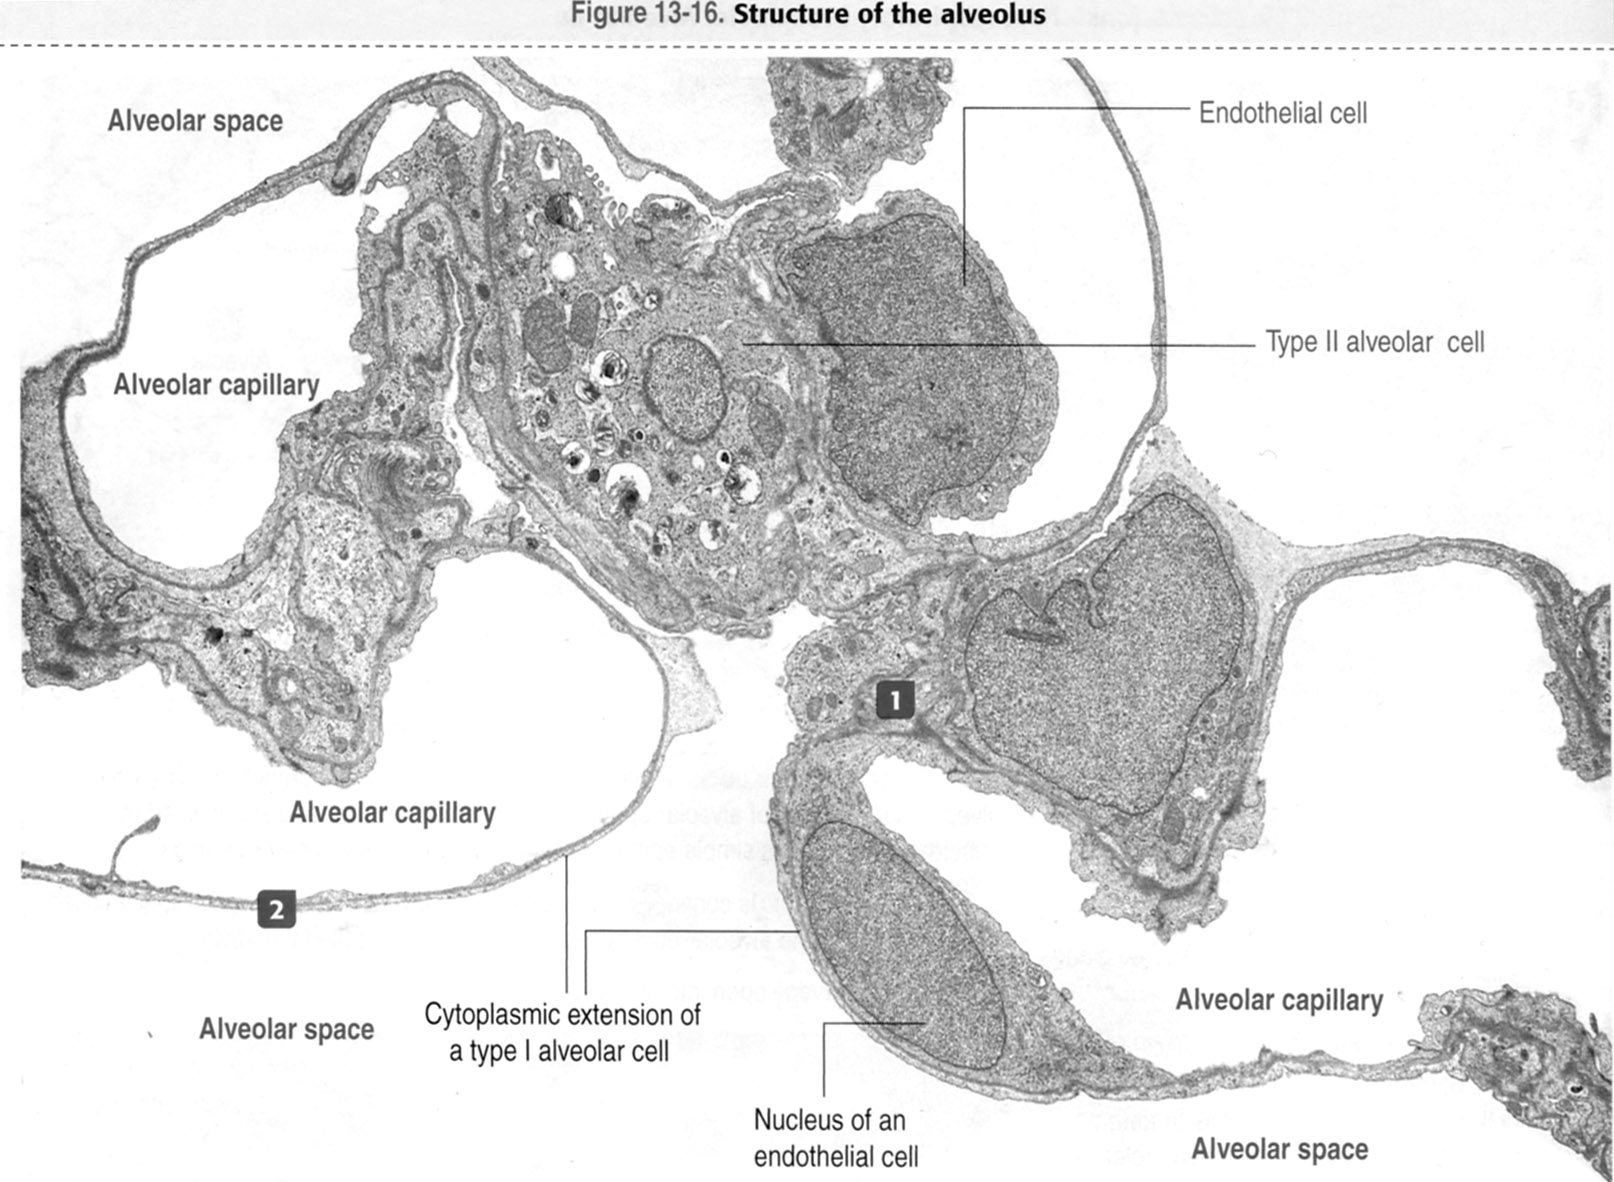

Light and electron microscopes allow us to see inside cells. A cell is a very tiny structure which exists in living bodies. Tissues affected by cancer cells under a microscope.